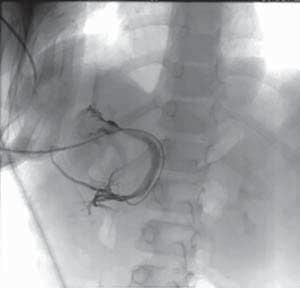

Rycina 119.4.